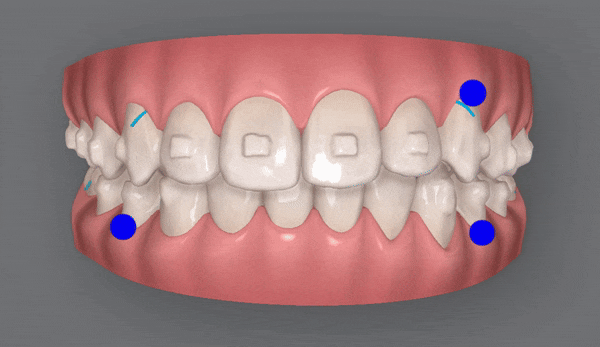

인비절라인 치료기간 22.01 ~ 24.06

세번째 클린체크를 마친 후 사진입니다

wow~!

치아 배열부터 교합까지

거의 완벽하게 마무리가 된것처럼 보이지만

꼼꼼한 닥터킴의 열정은 끝나지 않았는데요 ><

마지막 클린체크를 통해

마무리된 치아배열을 확인해 보실까요?

교정기간: 22/1~24/6

치열이 고르지 않고

송곳니가 도드라져 보였던 이전과는 달리,

청소년기인비절라인 교정 후

정중선이 맞아지고 치열이 가지런해지면서

보다 자연스러운 미소를 지어주었습니다.